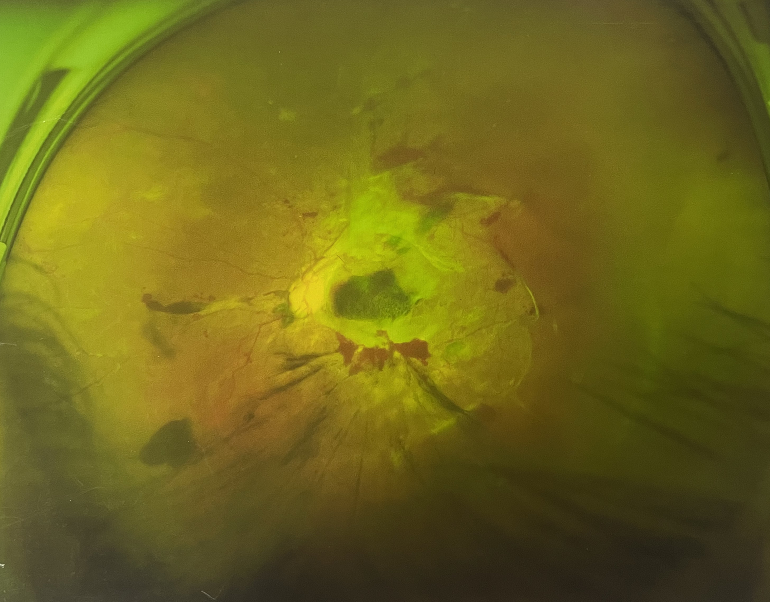

右眼術(shù)后

由于王女士的左眼沒有聽從醫(yī)生盡快做手術(shù)的建議,一直耽誤,從4月前的0.4視力逐漸下降到僅剩眼前手動,導(dǎo)致左眼發(fā)展到糖尿病視網(wǎng)膜病變VI期(屬于6期糖網(wǎng)中的晚期),已經(jīng)產(chǎn)生大量新生血管+纖維增值+廣泛牽拉性視網(wǎng)膜脫離,由于耽誤了病情,且病情發(fā)展異常迅速,導(dǎo)致目前左眼連保住眼球都很困難。

“而如果4月余前,左眼及時手術(shù)(當(dāng)時左眼病情比右眼輕,增殖膜還未累及黃斑),左眼將恢復(fù)的比右眼還好,甚至可以恢復(fù)到0.8或1.0,而現(xiàn)在連保住眼球的機(jī)會都很渺茫”,張小虎醫(yī)生表示實(shí)在可惜。

4個月前的左眼

左眼發(fā)展到糖尿病視網(wǎng)膜病變VI期